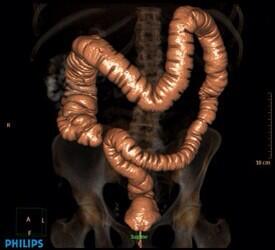

٢- سرطان القولون..

وهو رقم 5 في المملكة على مستوى النساء والرجال

أعراض السرطان خفيه أحيانا ويمكن تأويلها لأسباب أخرى أو يكون التشخيص متأخر

تبدأ الفحوصات عند 50 سنه وتكون على شكل..

منظار القولون..

وهو الفحص الكامل حيث يظهر شكل الأنسجة ووجود الأورام وموقعها مع إمكانية أخذ عينة في نفس الوقت في حالة وجود أي أورام..

وفي حالة وجود تاريخ مرضي او نزول دم من فتحة الشرج على المريض مراجعة الطبيب للتأكد من السبب..

منظار القولون لا يحتاج إعاده ل 10سنوات بعده